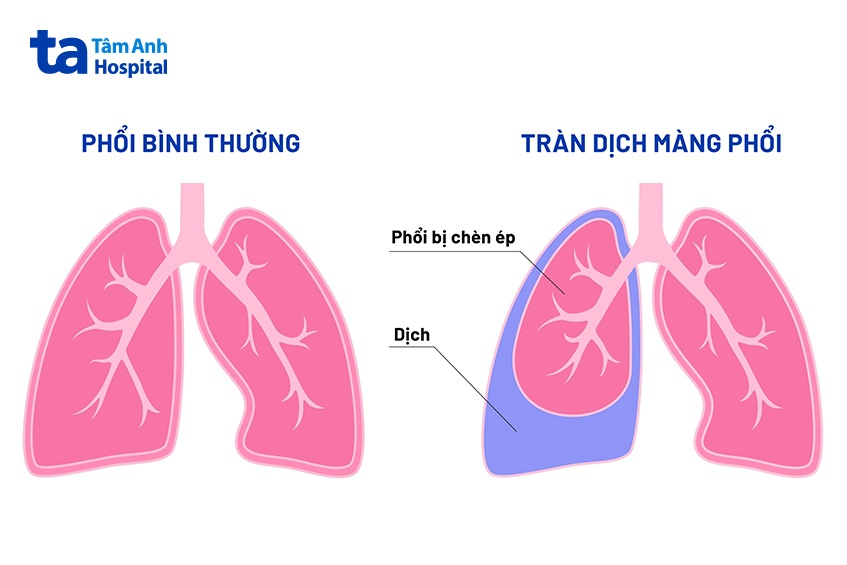

Viêm phổi ở trẻ sơ sinh, đặc biệt là viêm phổi do vi khuẩn có thể gây biến chứng tràn dịch màng phổi ở trẻ. Biến chứng này xảy ra khi trẻ không đáp ứng hoàn toàn với các phương pháp điều trị thông thường. Vi khuẩn lan ra màng phổi, tích tụ và gây nhiễm trùng, tạo thành ổ mủ, khiến trẻ khó hô hấp, nguy hiểm tính mạng. (5)